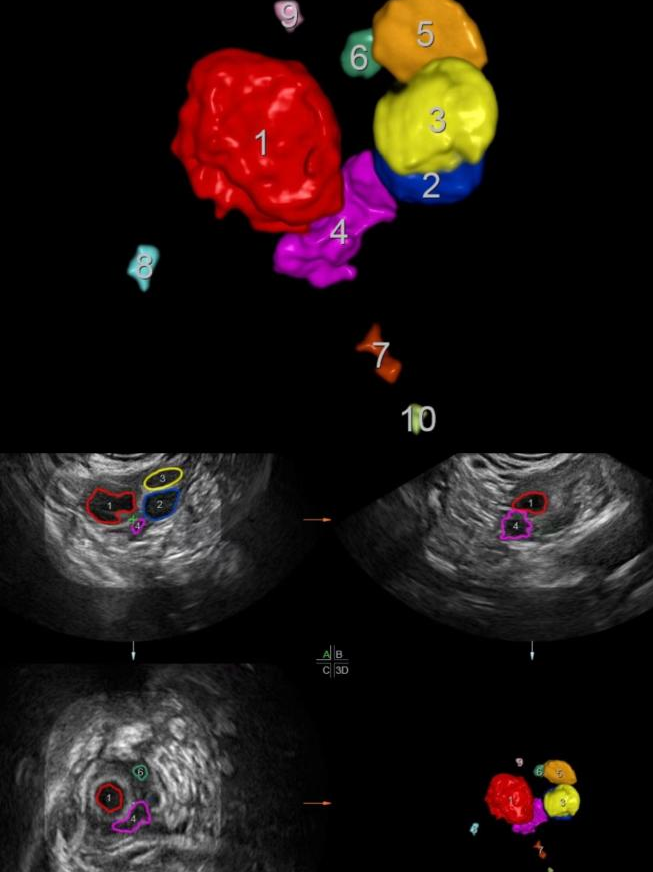

三维成像智能卵泡检测